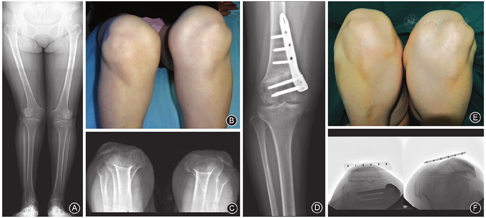

仔细触摸分辨股外侧肌腱与股中间肌腱之间的界限,将股外侧肌腱在髌骨上缘行"L"形切断(图1A);切断后向近端分离至股外侧肌的肌腹,将切断的股外侧肌腱在松弛位置与股中间肌腱缝合(图1B),以达到股外侧肌腱延长的目的。

确认髌骨在膝关节全范围屈伸活动时仍处于中立位后,行MPFL重建(图1C)。

轻度脱位1例患者(图2),术后膝关节影像学检查结果示髌骨适合角由术前72°改善为术后5°,Caton-Deschamps指数为0.82,TT-TG为28 mm,股骨滑车沟角150°。因患者未行胫骨结节移位和股骨滑车成形术,故Caton-Deschamps指数、TT-TG、股骨滑车沟角均未变化。

中度脱位6例患者(图3),术后膝关节影像学检查结果示髌骨适合角由术前平均82.2°±11.7°改善为术后6.9°±26.4°,平均减少75.3°,术前与术后比较差异有统计学意义(t=4.064,P=0.027)。Caton-Des-champs指数由术前平均0.77(范围,0.64~1.14)改善为术后平均0.78(范围,0.75~1.14)(P=0.109),TT-TG由术前平均(18.8±2.2)mm改善为术后(15.7±5.9)mm(t=1.000,P=0.423),股骨滑车沟角由术前153.7°±8.8°改善为术后153.6°±8.5°(t=0.042,P=0.969);以上各指标术前与术后比较差异均无统计学意义。

重度脱位29例患者(图4),术后膝关节影像学检查结果示髌骨适合角由术前平均75.0°±27.3°改善为术后0.0°±21.0°,平均减少75.0°(t=5.735,P=0.000);Caton-Deschamps指数由术前平均0.76±0.24改善为术后平均1.06±0.24,平均增加0.30(t=-5.655,P=0.000);TT-TG由术前平均(22.9±5.1)mm改善为术后(6.0±4.9)mm,平均减少16.9 mm(t=11.109,P=0.000);以上各指标术前与术后比较差异有统计学意义。股骨滑车沟角术前155.9°±11.1°,术后148.5°±11.1°,术前与术后比较差异无统计学意义(t=1.877,P=0.093)。